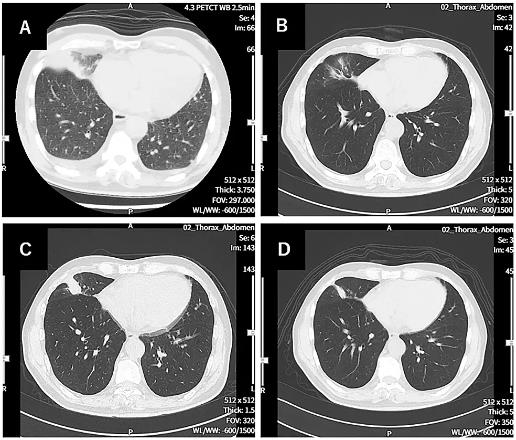

知名医学杂志《Cureus》报道了一个“WT1-DC治疗全身转移的肺癌”的案例分析,该患者为1例69岁男性,患右肺中叶IV期鳞状细胞癌,且已出现双侧肾上腺转移、多发性肝及骨转移症状,目前已无法耐受手术、放疗等传统治疗手段。万念俱灰下,他入组接受了“WT1-DC联合(卡铂AUC6+紫杉醇)化疗”,结果显示如下:

1、胸部CT:患者在刚诊断时的胸部CT示,右下肺原发性肺癌,伴左右胸腔积液;治疗第114天,肺部原发病灶几乎消失;但此后原发病灶有一定的复发倾向(治疗第213天);不过值得欣慰的是,在治疗第338天复查显示,原发性及复发性病灶缩小(详见下图)。

▲图源“Cureus”,版权归原作者所有,如无意中侵犯了知识产权,请联系我们删除

注:图A、B、C、D分别代表诊断时、治疗第114天、治疗第213天、治疗第338天的CT图像。